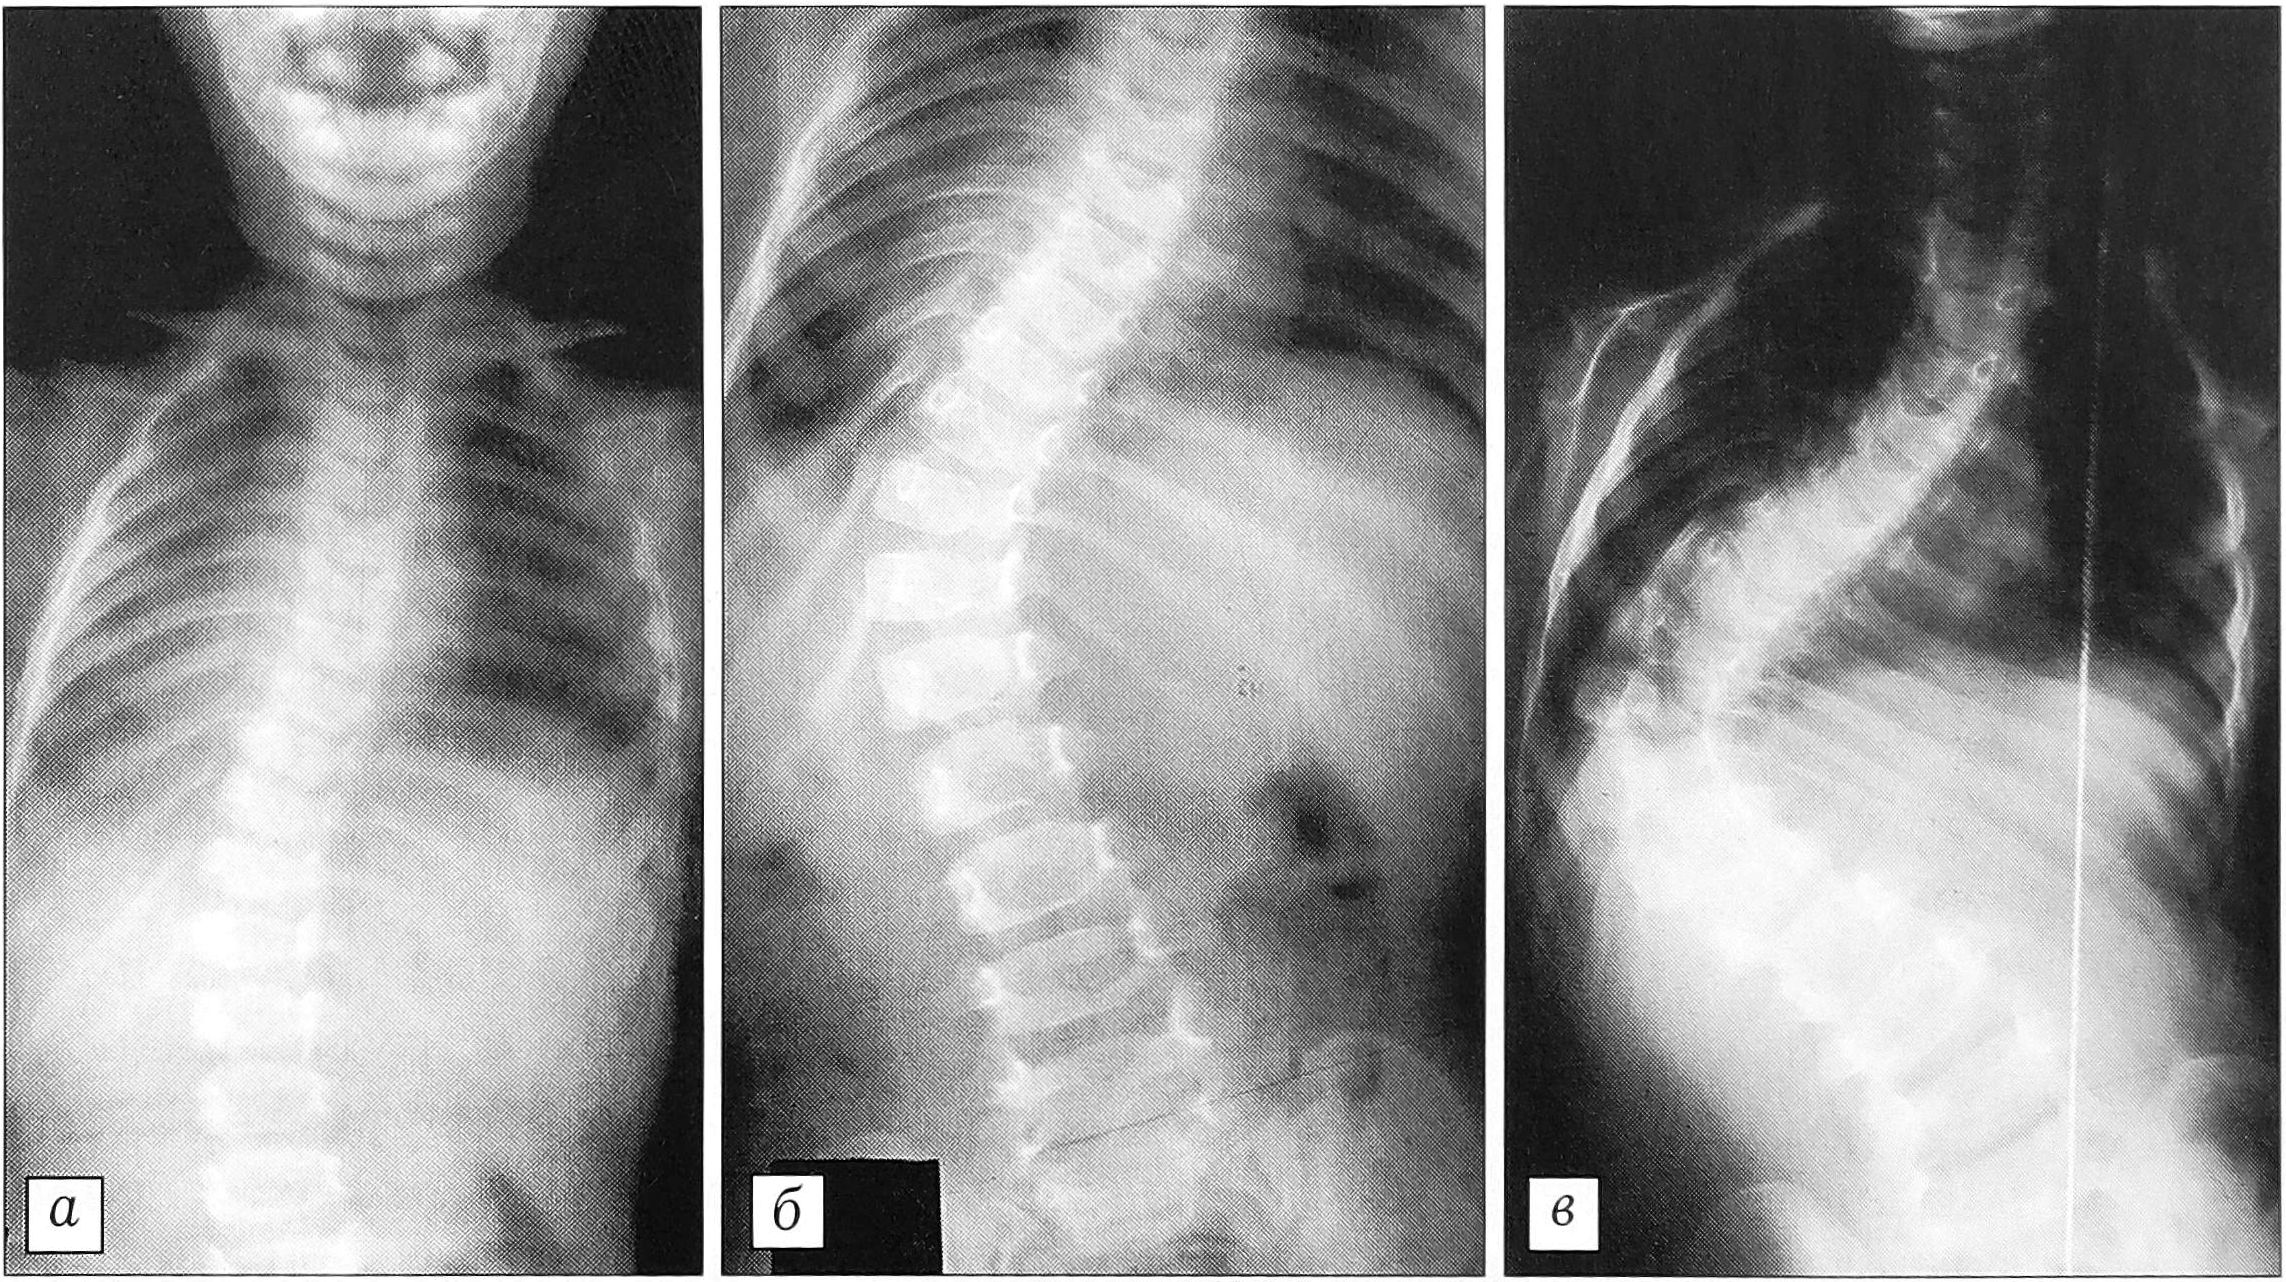

Мы глубоко убеждены в том, что несмотря на все трудности и проблемы, связанные с ранним лечением идиопатического сколиоза, возрастной порог операбельности должен быть максимально снижен, так как при злокачественно прогрессирующих инфантильных и ювенильных сколиозах консервативное лечение неприемлено (рис. 1).

Рис. 1. Больная Г-ра. Злокачественное прогрессирование инфантильного сколиоза исключает возможность выжидательной тактики: в возрасте 1 года деформация 23° (а), в 2 года — 48° (б), в 4 года — 110° (в).